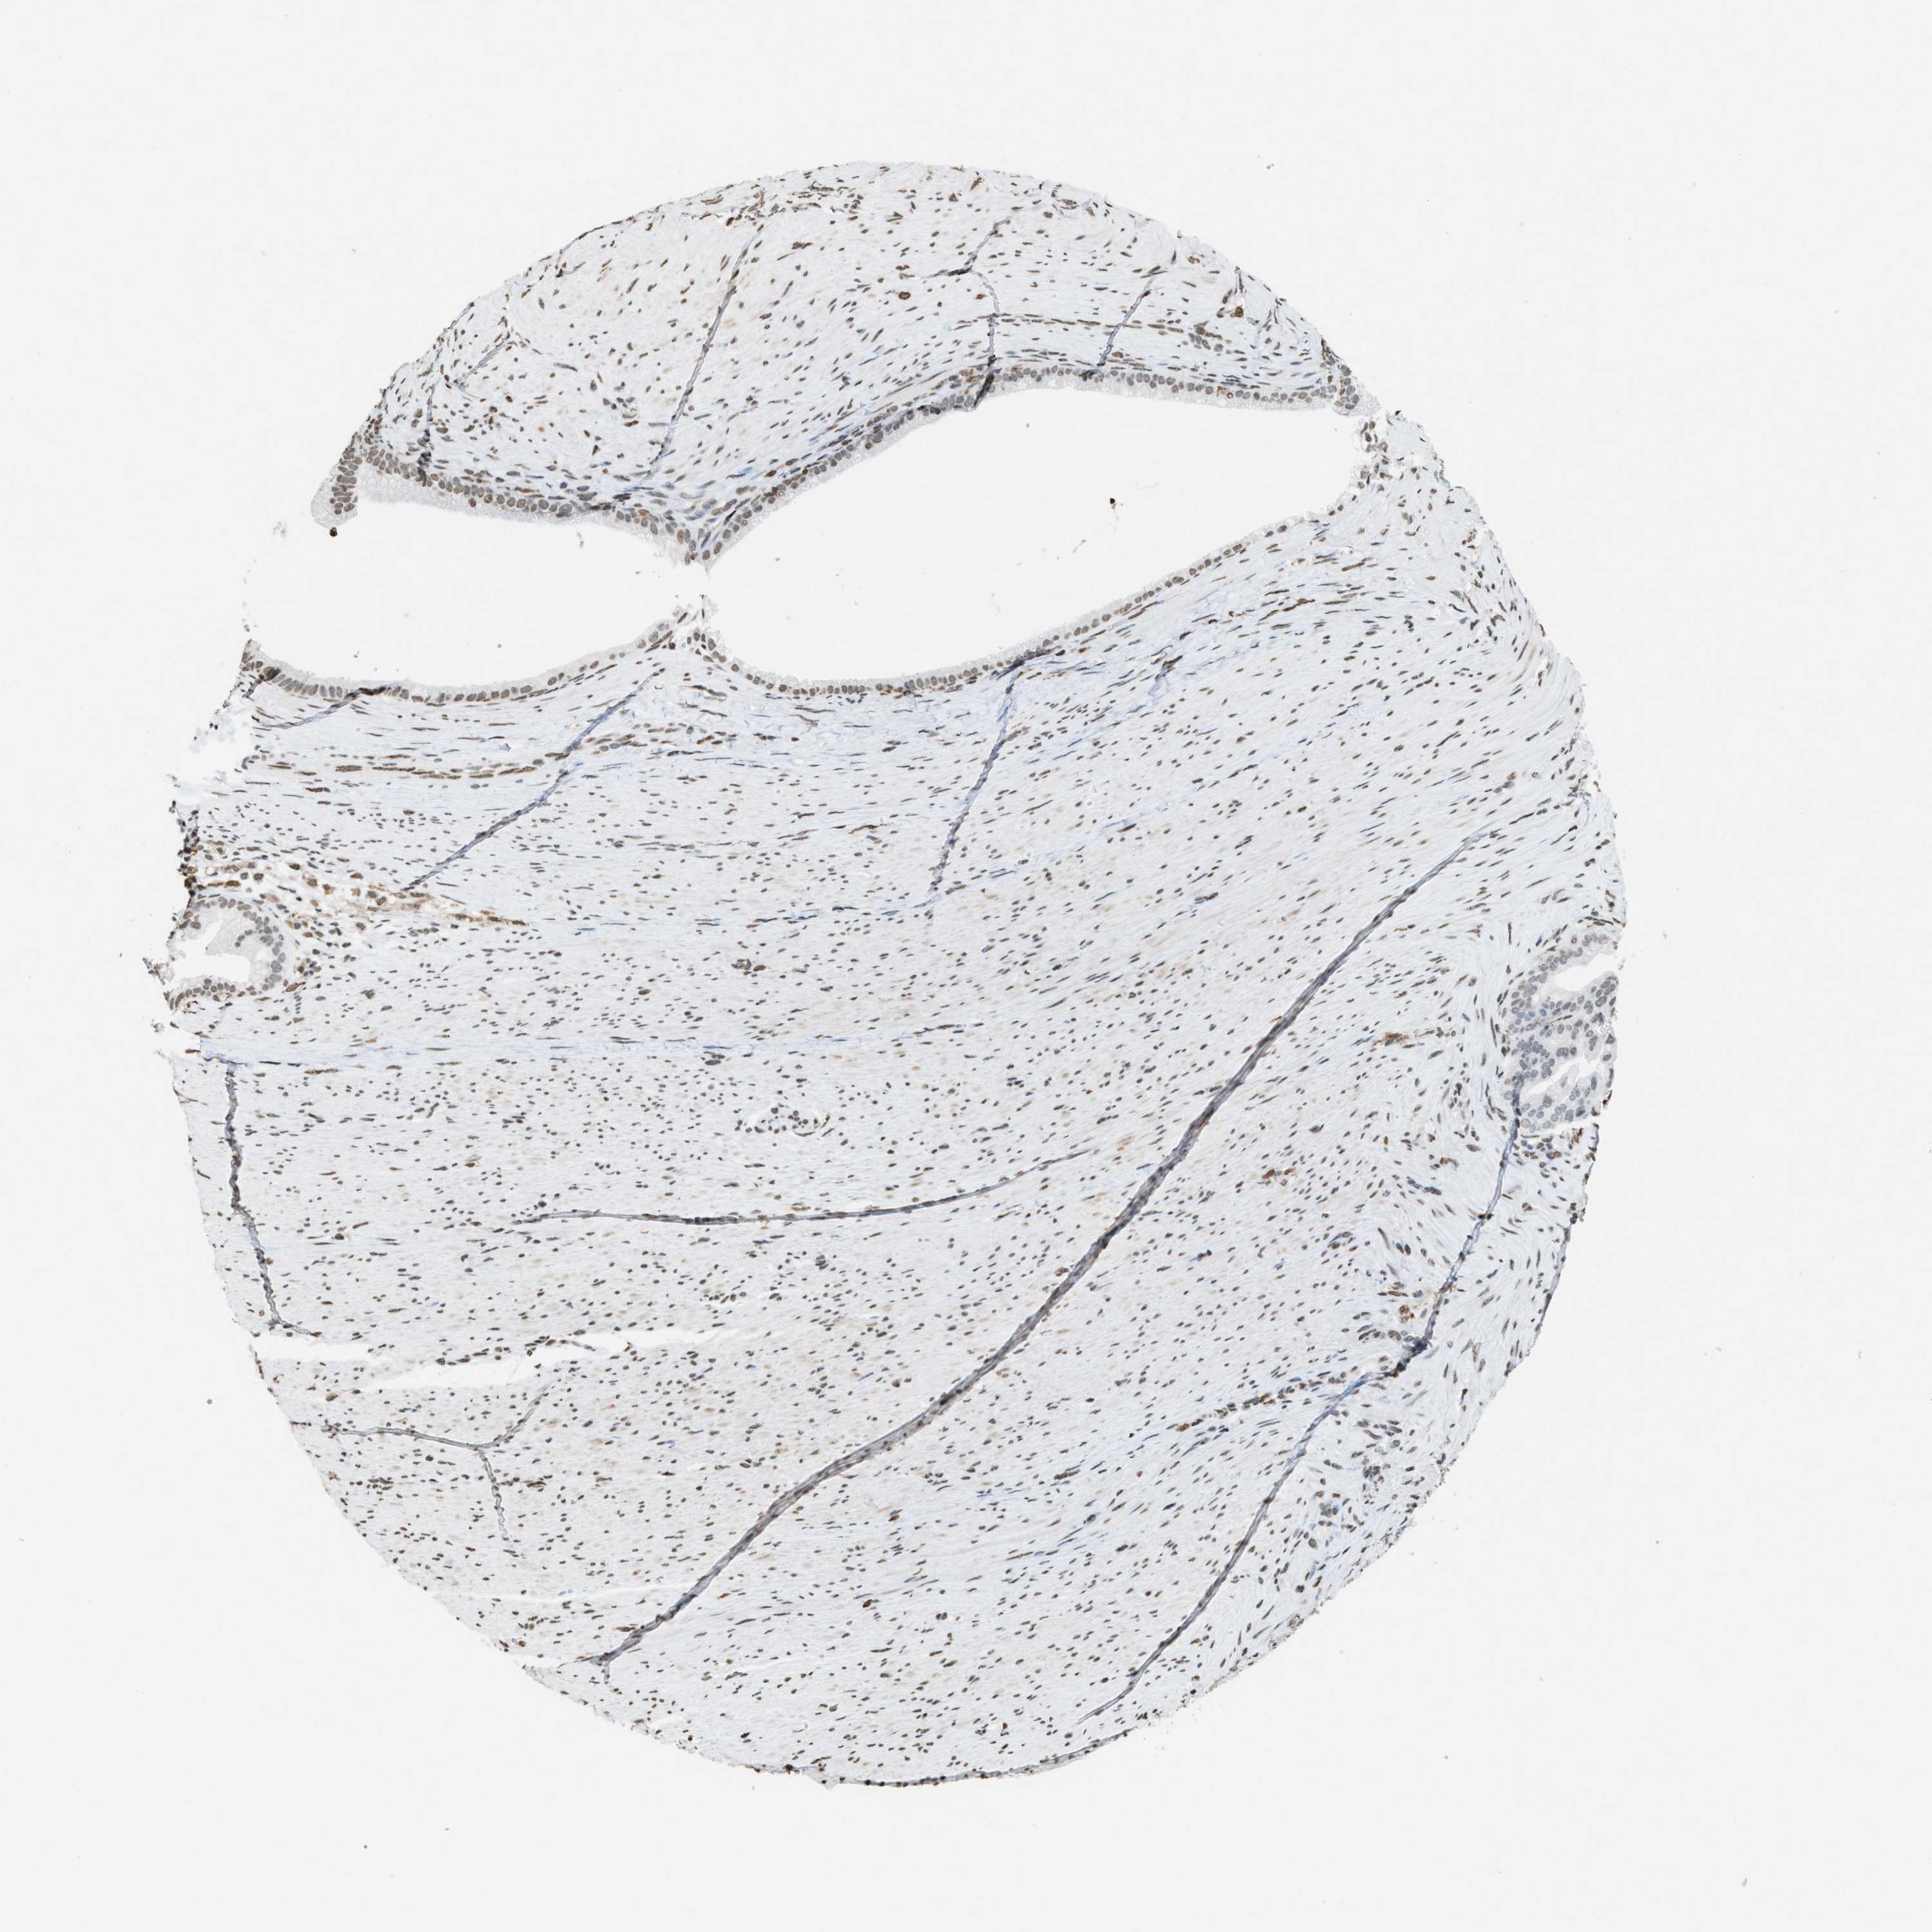

PANCREATIC CANCER - Protein expressioni

A mouse-over function shows sample information and annotation data. Click on an image to view it in a full screen mode. Samples can be filtered based on level of antibody staining by selecting one or several of the following categories: high, medium, low and not detected. The assay and annotation is described here.

Note that samples used for immunohistochemistry by the Human Protein Atlas do not correspond to samples in the TCGA dataset.

Antibody stainingi

Antibody staining in the annotated cell types in the current human tissue is reported as not detected, low, medium, or high, based on conventional immunohistochemistry profiling in selected tissues. This score is based on the combination of the staining intensity and fraction of stained cells.

Each image is clickable and will lead to virtual microscopy that enables deeper exploration of all samples and also displays staining intensity scores, fraction scores and subcellular localization as well as patient and tissue information for each sample.

Antibody HPA021816

Antibody CAB002209

Staining

High

Medium

Low

Not detected

Intensity

Strong

Moderate

Weak

Negative

Quantity

>75%

75%-25%

<25%

None

Location

Nuclear

Cytoplasmic/membranous

Cytoplasmic/membranous,nuclear

Adenocarcinoma, NOS

Adenocarcinoma, metastatic, NOS